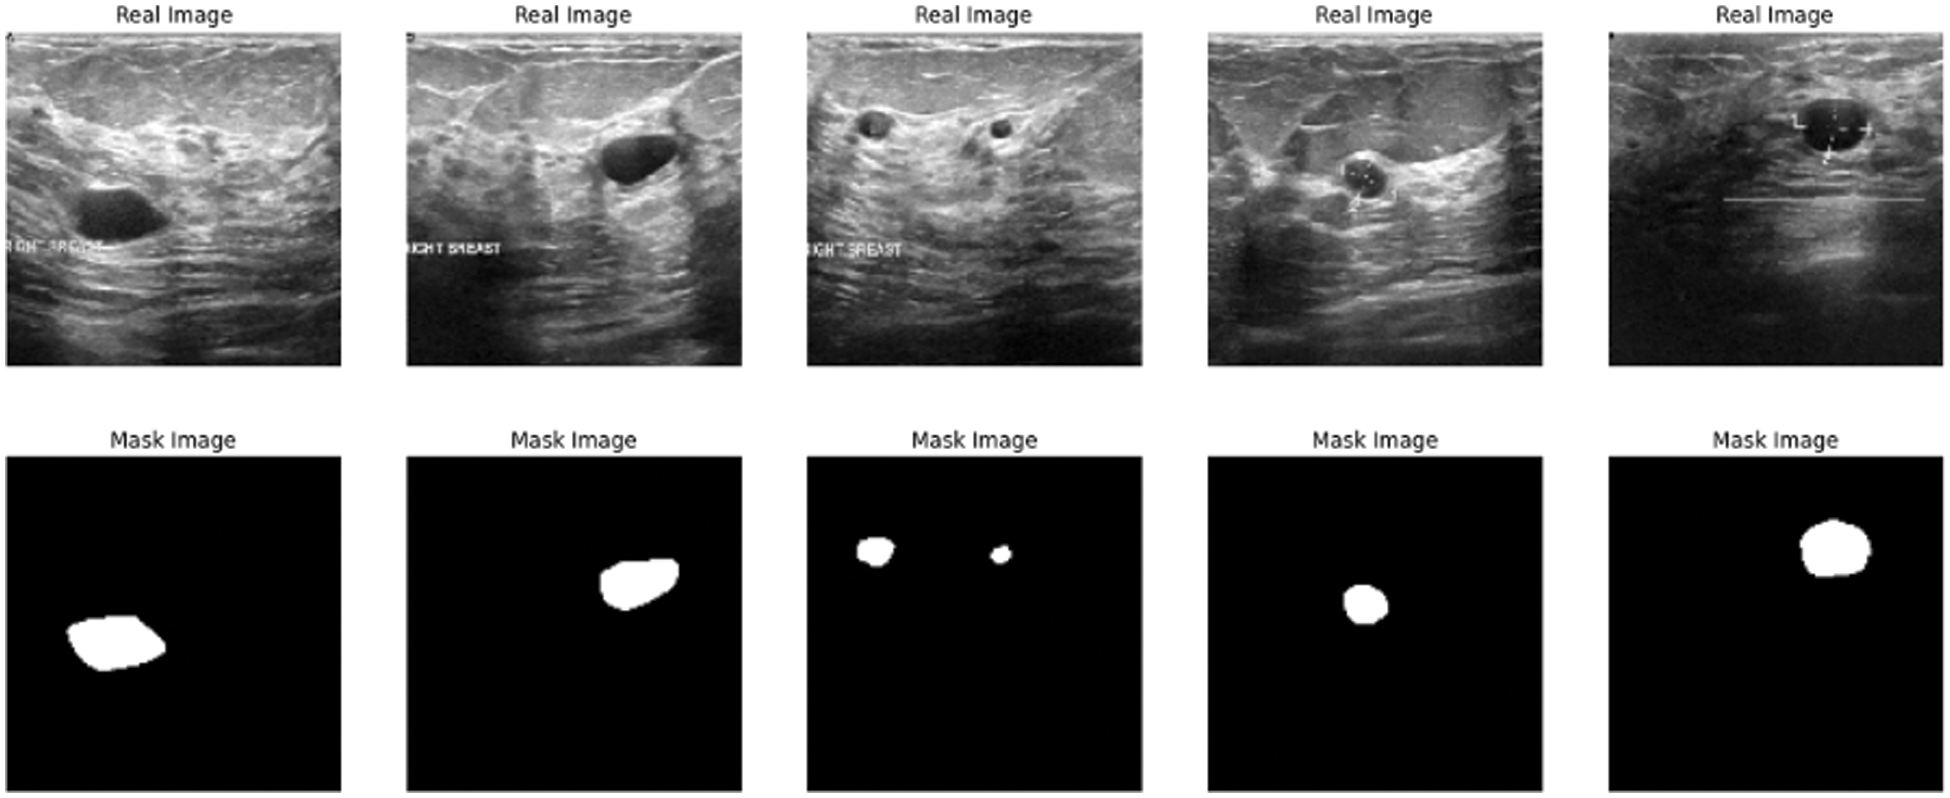

The paper used a dataset from Kaggle called breast ultrasound image dataset, which is being used for segmentation and detection. The image in the used dataset is collected for women of different and various ages in the range between 18 and 75. The dataset contains three types of ultrasound images benign tumor, malignant tumor, and normal. The dataset contains around 750 images in portable network graphics (PNG) format with size 500 * 500 [25]. The images are divided into two parts images for tumors and the masks Fig. 2 shows some results from the exploration of the five images from the dataset.

Figure 2: Data exploration of dataset